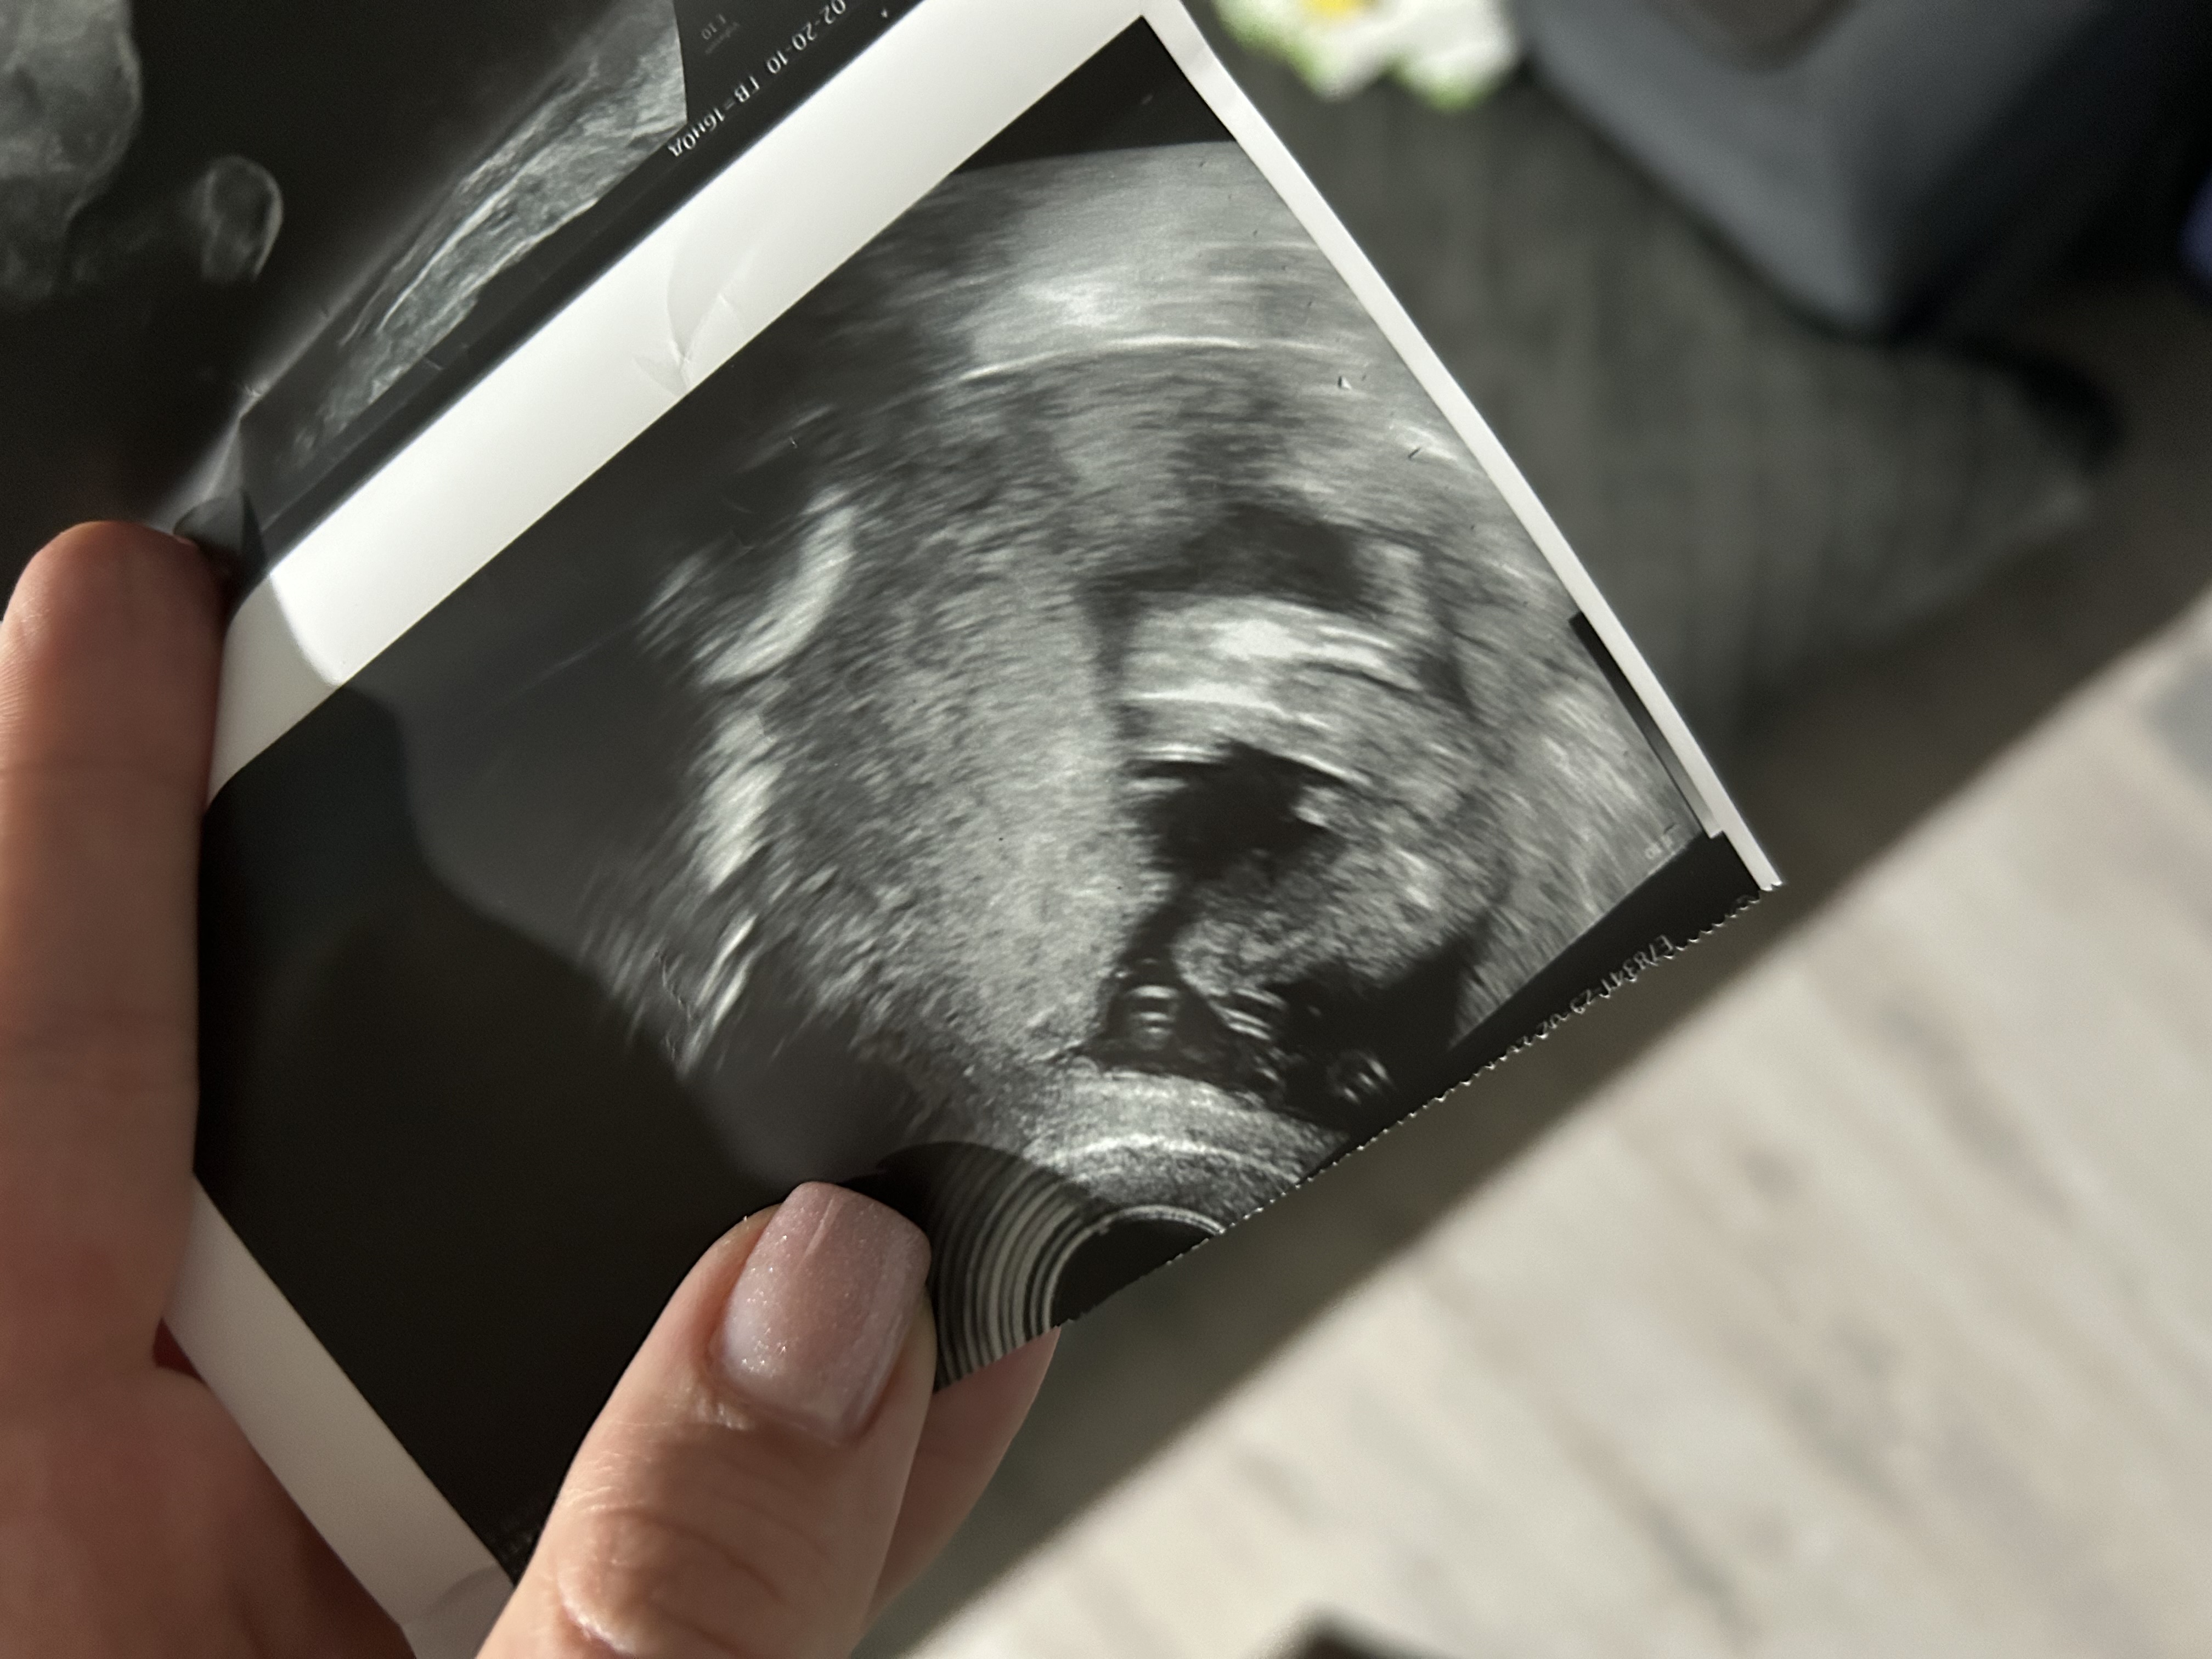

Девочки,точно же мальчик,да ?😅🙈

Да, мальчик )) есть фото с такого же ракурса с девочкой там все пусто между ножек))

У меня с младшим в 16 недель прям такое же фото было, один в один )

Кристина , вот наша фотка в 16 недель, тоже уже никаких сомнений не было: Изображение

Ольга, ну да,такие же причиндалы 🤭